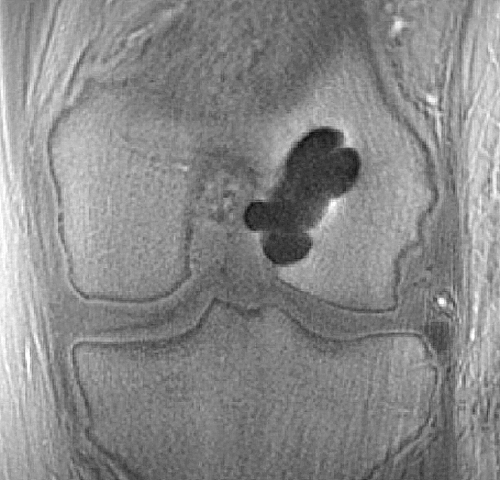

In this original research study (published on J Comput Assist Tomogr 2015;39: 637–642), we investigated sensitivity of novel UTE T1rho sequence to degeneration of human menisci, simulated usi ...